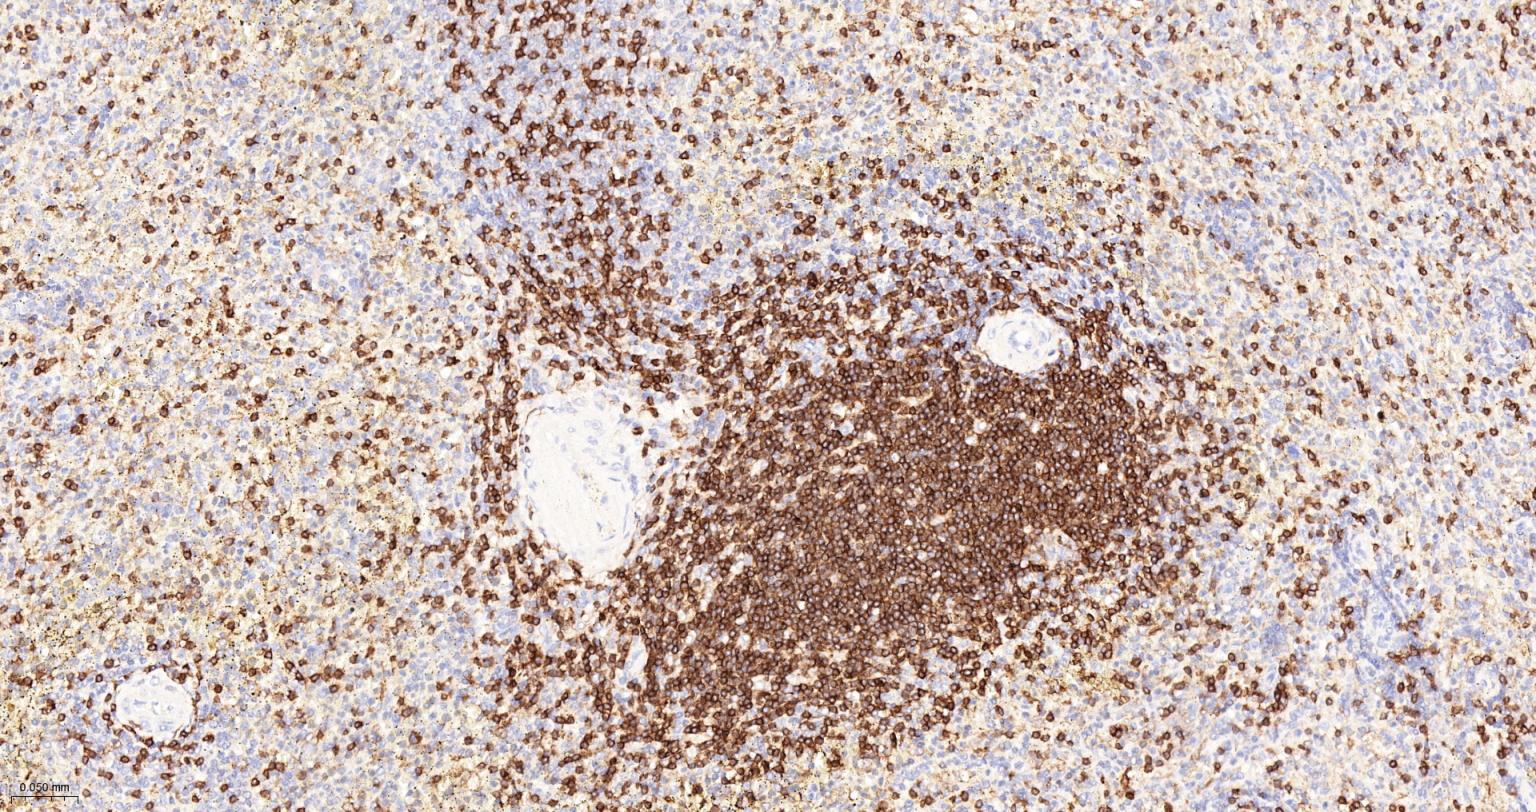

CD3E Recombinant Rabbit mAb

CD3/CD3-ε重组兔单抗

IHC-PHuman, Mouse, Rat1:500-2000

CD3e molecule, epsilon is also known as CD3E, is a T-cell surface single-pass type I membrane glycoprotein. CD3E contains 1 Ig-like (immunoglobulin-like) domain and 1 ITAM domain. CD3E, together with CD3-gamma, CD3-delta and CD3-zeta, and the T-cell receptor alpha/beta and gamma/delta heterodimers, forms the T cell receptor-CD3 complex. This complex plays an important role in coupling antigen recognition to several intracellular signal-transduction pathways. The genes encoding the epsilon, gamma and delta polypeptides are located in the same cluster on chromosome 11. The epsilon polypeptide plays an essential role in T-cell development. CD3E plays an essential role in T-cell development, and defects in CD3E gene cause severe immunodeficiency. CD3E gene has also been linked to a susceptibility to type I diabetes in women. CD3E has been shown to interact with TOP2B, CD3EAP and NCK2.